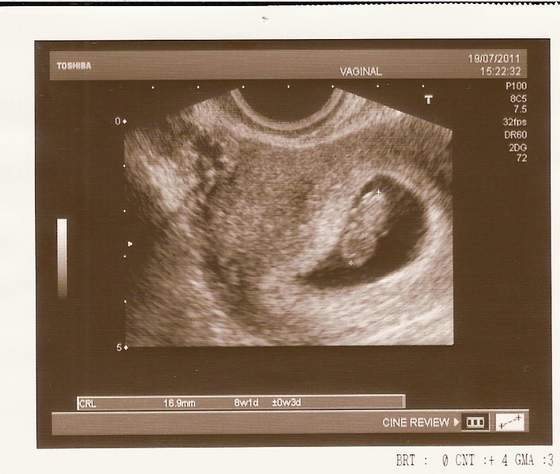

usg

Ja i moje Skarby :)